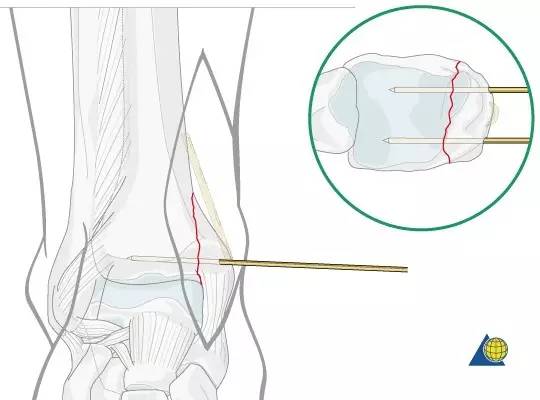

复位内踝骨折块之前,需仔细清理骨折端。关节面如存在塌陷,可翻书样将内踝骨折块掀开,暴露并复位关节面、植骨。

两枚克氏针临时固定,在关节线上方 1 cm 水平进针,一前一后,尽量靠前靠后,为钢板置于两枚克氏针之间预留空间。